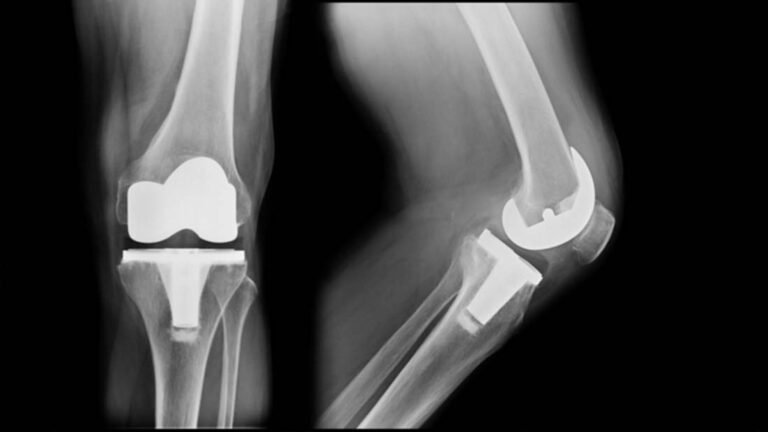

X-rays are commonly used to determine stress fracture. Sometimes, the stress fracture cannot be seen on regular x-rays or will not show up for several weeks after the pain starts. Occasionally, a computed topography (CT) scan or magnetic resonance imaging (MRI) will be necessary.